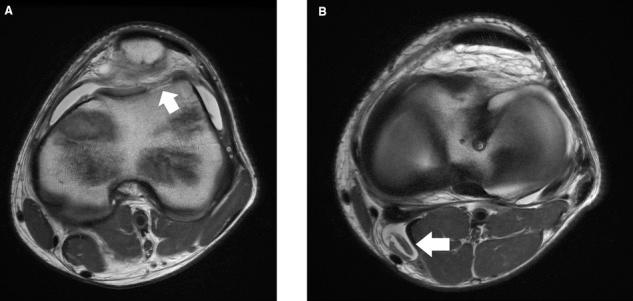

Although disorders of the patellofemoral joint are common in the athlete, their management can be challenging and require a thorough physical examination and radiologic evaluation, including advanced magnetic resonance imaging techniques.

Physical examination and imaging evaluation including standard radiographs are crucial in identifying evidence of malalignment or instability. Magnetic resonance imaging provides valuable information about concomitant soft tissue injuries to the medial stabilizers as well as injuries to the articular cartilage, including chondral shears and osteochondral fractures. Quantitative magnetic resonance imaging assessing the ultrastructure of cartilage has shown high correlation with histology and may be useful for timing surgery.

Evaluation of patellofemoral disorders is complex and requires a comprehensive assessment. Recent advancements in imaging have made possible a more precise evaluation of the individual anatomy of the patient, addressing issues of malalignment, instability, and underlying cartilage damage.